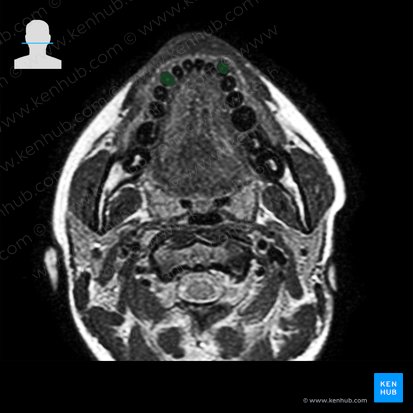

O canino é o terceiro dente a partir do centro (incisivo central > incisivo lateral > canino). Ele é um dente afiado, com uma única ponta ou cúspide, cuja função é rasgar ou perfurar o alimento. Os humanos possuem quatro dentes caninos: dois caninos superiores (direito e esquerdo) e dois caninos inferiores (direito e esquerdo).

Assim como os outros dentes, os caninos têm uma coroa (a parte acima da gengiva), um colo e uma raiz (parte dentro do osso). A superfície externa é uma fina camada de esmalte que cobre a dentina interna. Existe um núcleo central na cavidade pulpar que está conectado a um canal radicular ricamente vascularizado e inervado.